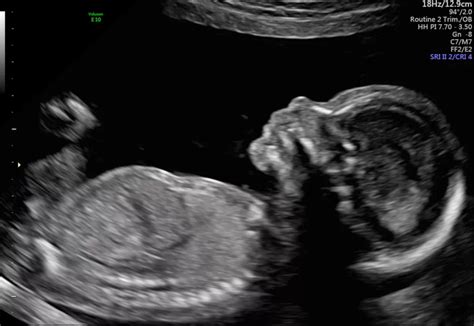

Hey guys! So, you’re heading in for your anatomy scan, also known as the 20-week ultrasound. It’s a pretty big deal, right? This is the scan where the sonographer takes a good, long look at your little one, checking all their major organs and body parts to make sure everything is developing as it should. It’s exciting because you get to see your baby in more detail than ever before, and for many, it’s the first time you’ll find out the sex! But let’s be real, it’s also a time when a lot of questions and maybe even a little anxiety can bubble up. One of the big questions on many parents’ minds is: how common is bad news at the 20-week scan? It’s totally normal to wonder about this. We’re all hoping for a perfectly healthy baby, and the thought of something being amiss can be really unsettling. So, let’s dive into what this scan is all about, what the ‘bad news’ might entail, and just how often these unexpected findings actually occur.

Alright, let’s get into the nitty-gritty of what actually happens during your anatomy scan. The sonographer is basically performing a super detailed, head-to-toe (or should we say, toe-to-head!) examination of your developing baby. They’re looking at about 20 different areas, and it’s pretty incredible what they can see. They’ll check the baby’s brain, face (including lips and palate), spine, heart (four chambers!), lungs, stomach, intestines, kidneys, bladder, and limbs (arms, legs, hands, feet). They’ll also measure the baby’s head circumference, abdominal circumference, and femur (thigh bone) length to ensure growth is on track. The placenta is examined to check its location (making sure it’s not covering the cervix, which would be placenta previa) and appearance. The amount of amniotic fluid is also assessed – too much or too little can sometimes indicate a problem. They’ll also check the umbilical cord for the number of blood vessels. The goal here is to catch any potential physical abnormalities or structural differences that might require attention. This could range from something relatively minor, like a small hole in the heart that often closes on its own, to more significant concerns like spina bifida or certain genetic syndromes. It’s a comprehensive checklist, and they’re moving through it methodically. Keep in mind that the quality of the images can depend on the baby’s position and the amount of amniotic fluid, so sometimes they might need you to shift positions, have a drink of cold water, or even do a little jumping jack routine to get the baby to move! It’s all part of the process to get the best possible view. This scan is a vital part of prenatal care because it allows for early detection of potential issues, which can lead to timely intervention and better outcomes for your baby.